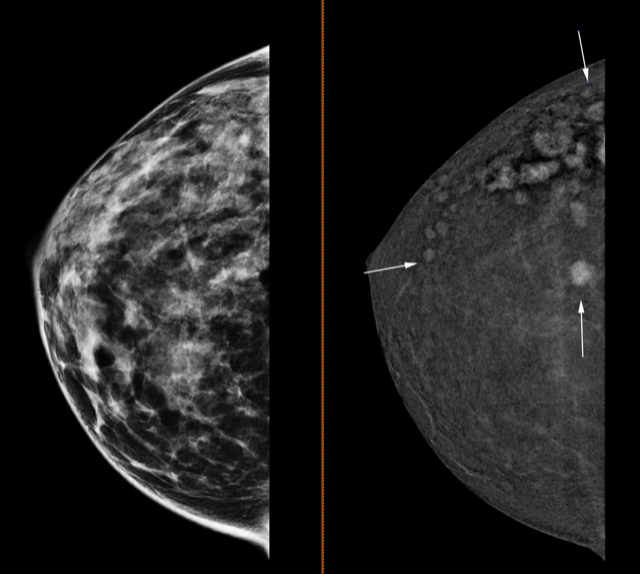

El Hospital Universitario del Vinalopó incorpora un mamógrafo 3D con contraste capaz de detectar tumores de solo cuatro milímetros

La nueva tecnología ofrece a las mujeres que han padecido un cáncer de mama “las máximas garantías de que no ha aparecido ninguna otra lesión, por pequeña que sea”